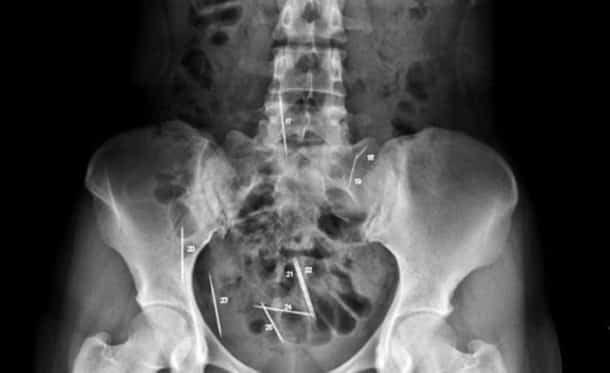

Accident, incident de pistolet à clous ou introductions douteuses de choses douteuses dans des parties douteuses de leur corps…voilà un petit aperçu de ce que voient les médecins au quotidien…

Certaines radiographies sont impressionnantes mais relèvent d’accidents…d’autres en revanche…